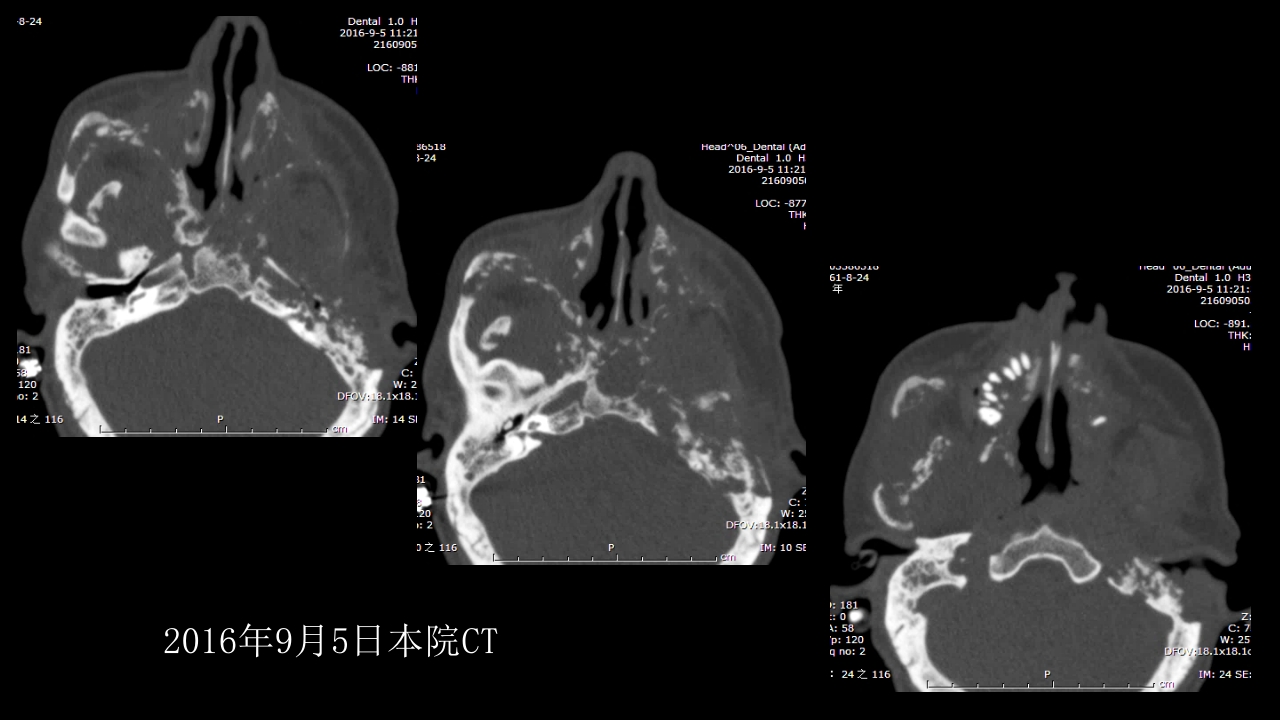

没有见过的弥漫性的骨质破坏